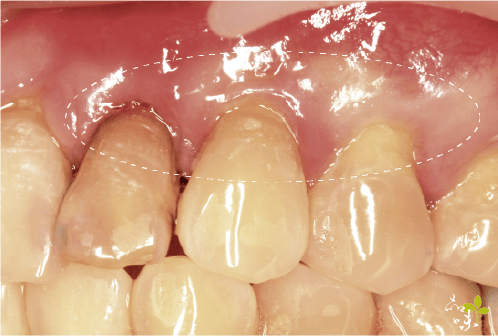

牙齦萎縮的過程很慢,不太容易被察覺,很多患者都是覺得最近吃東西、喝飲料感到痠痛敏感來就診,醫生檢查後,可能發現有這幾種狀況:

牙齦萎縮的現象

- 某幾顆牙齒齒頸部露出、形成一個 V 字型。

- 假牙邊緣外露,牙冠以下露出來。

- 牙縫有變大的傾向。